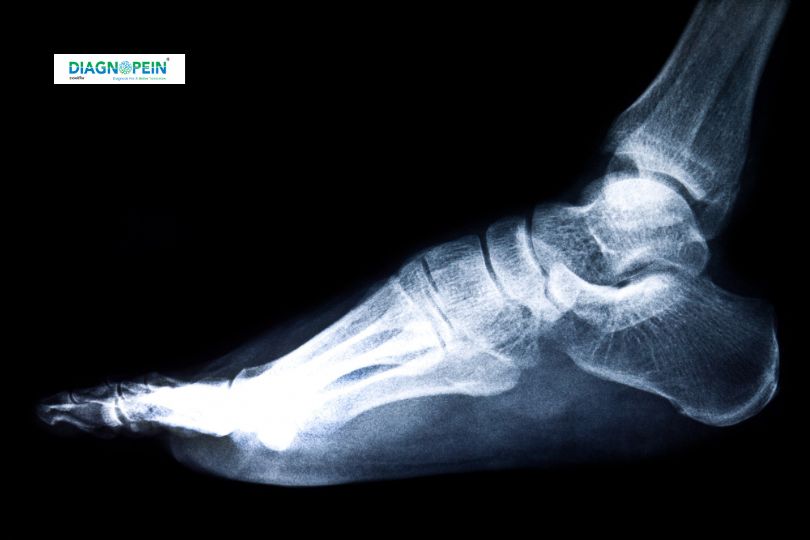

The FOOT AP/LAT. VIEW refers to the Anteroposterior (AP) and Lateral (LAT) radiographic views of the foot, which are essential x-ray projections used in medical imaging to diagnose injuries, deformities, and pathological conditions in the foot. The AP view provides a front-to-back image, while the LAT view offers a side profile, together giving a complete assessment of bone alignment, joint spaces, and soft tissue structures.

Foot conditions such as fractures, arthritis, bone spurs, infections, and congenital deformities require precise imaging for accurate diagnosis and effective treatment planning. FOOT AP/LAT. VIEW is critical because it enables doctors to see multiple angles of bones, joints, and soft tissues, helping to:

1. Detect fractures and dislocations with clarity

2. Assess joint spaces in conditions like arthritis

3. Identify bone abnormalities or infections

4. Guide surgical planning and monitor healing progress

Without these views, critical details could be missed, resulting in misdiagnosis or delayed treatment.